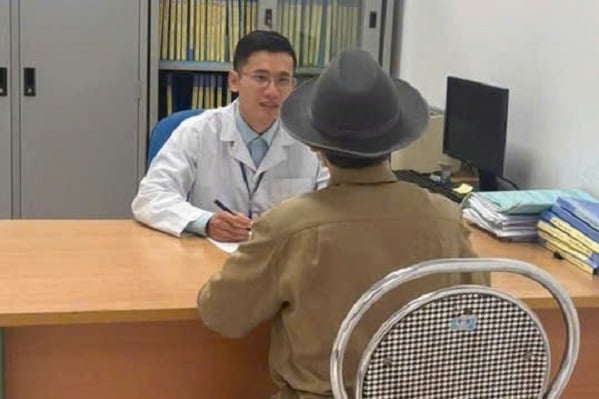

លោកវេជ្ជបណ្ឌិត ថាច ផ្តល់ដំបូន្មានដល់អ្នកញៀនថ្នាំលើការព្យាបាលដោយមេតាដូន។ រូបថត៖ CDC ខេត្ត Tuyen Quang។